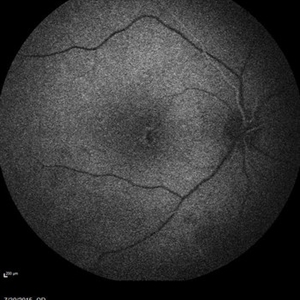

Retinal Dystrophy of 24-Year-Old Male/ Red Free OD

Nov 25 2015 by Zach Dupureur

Fluorescein angiography of a 24-year-old male. Juvenile retinoschisis on OCT. FA shows outer retinal staining. Could be associated with Goldman Farve Syndrome.

Photographer: Zach Dupureur OCT-C

Imaging device: Heidelberg Spectralis

Condition/keywords: Goldmann-Favre Syndrome, juvenile retinoschisis, retinal dystrophy